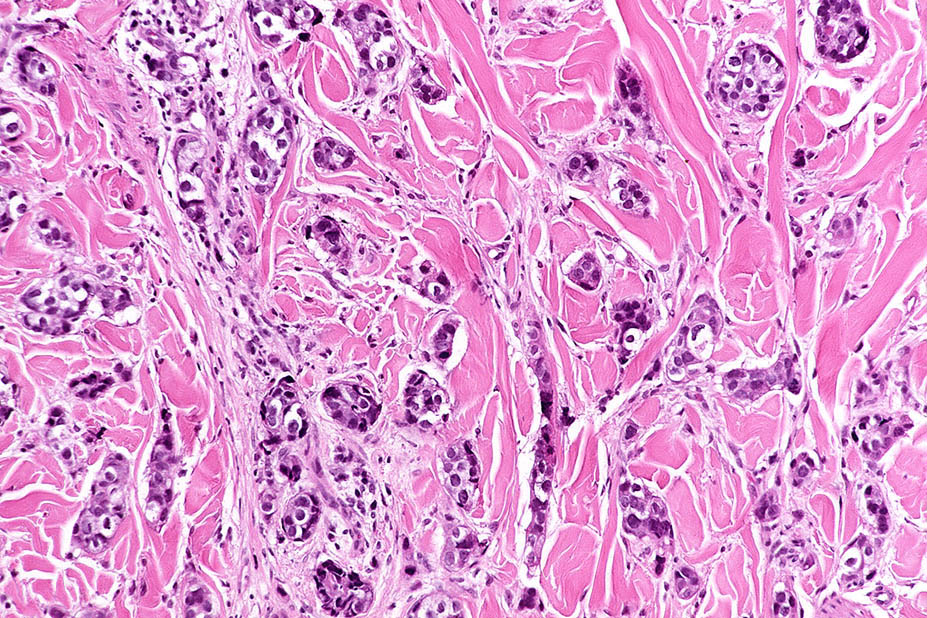

Breast cancer = سرطان الثدي